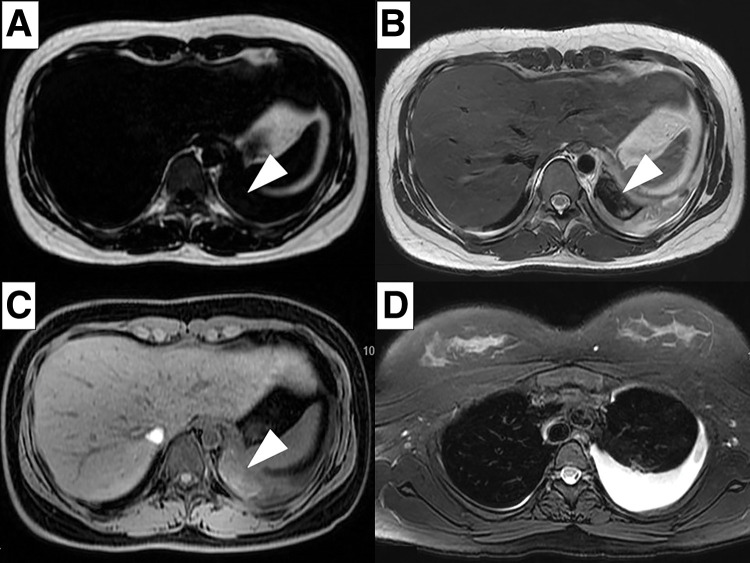

Case presentation: An 18-year-old female presented with a fever and sudden left-sided back pain. Blood tests revealed leukocytosis and an elevated C-reactive protein. Imaging studies identified a well-circumscribed cyst along the left diaphragm, suspected to be an infected bronchogenic cyst. Magnetic resonance imaging 2 days later indicated disease progression with concomitant empyema, prompting emergency surgery. Using the confronting upside-down monitor setting, the cyst was resected. Thoracoscopic findings revealed a dark red cyst and bloody pleural effusion. The surgery was uneventful, and the patient was discharged on postoperative day 2. Bacterial cultures of the pleural effusion and cystic content were negative, and histopathological analysis confirmed the diagnosis of a hemorrhagic bronchogenic cyst.